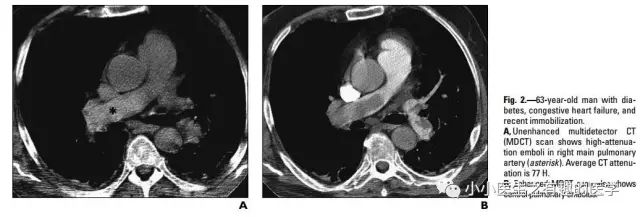

作者单位:Department of Radiology, University of Washington MedicalCenter, University of Washington School of Medicine(华盛顿医科大学)。

翠花上菜,学者上图。

发现嫌疑犯,立即逮捕。

增强CT对比,一目了然。

上面的患者,增强CT放大了。

星号的地方。